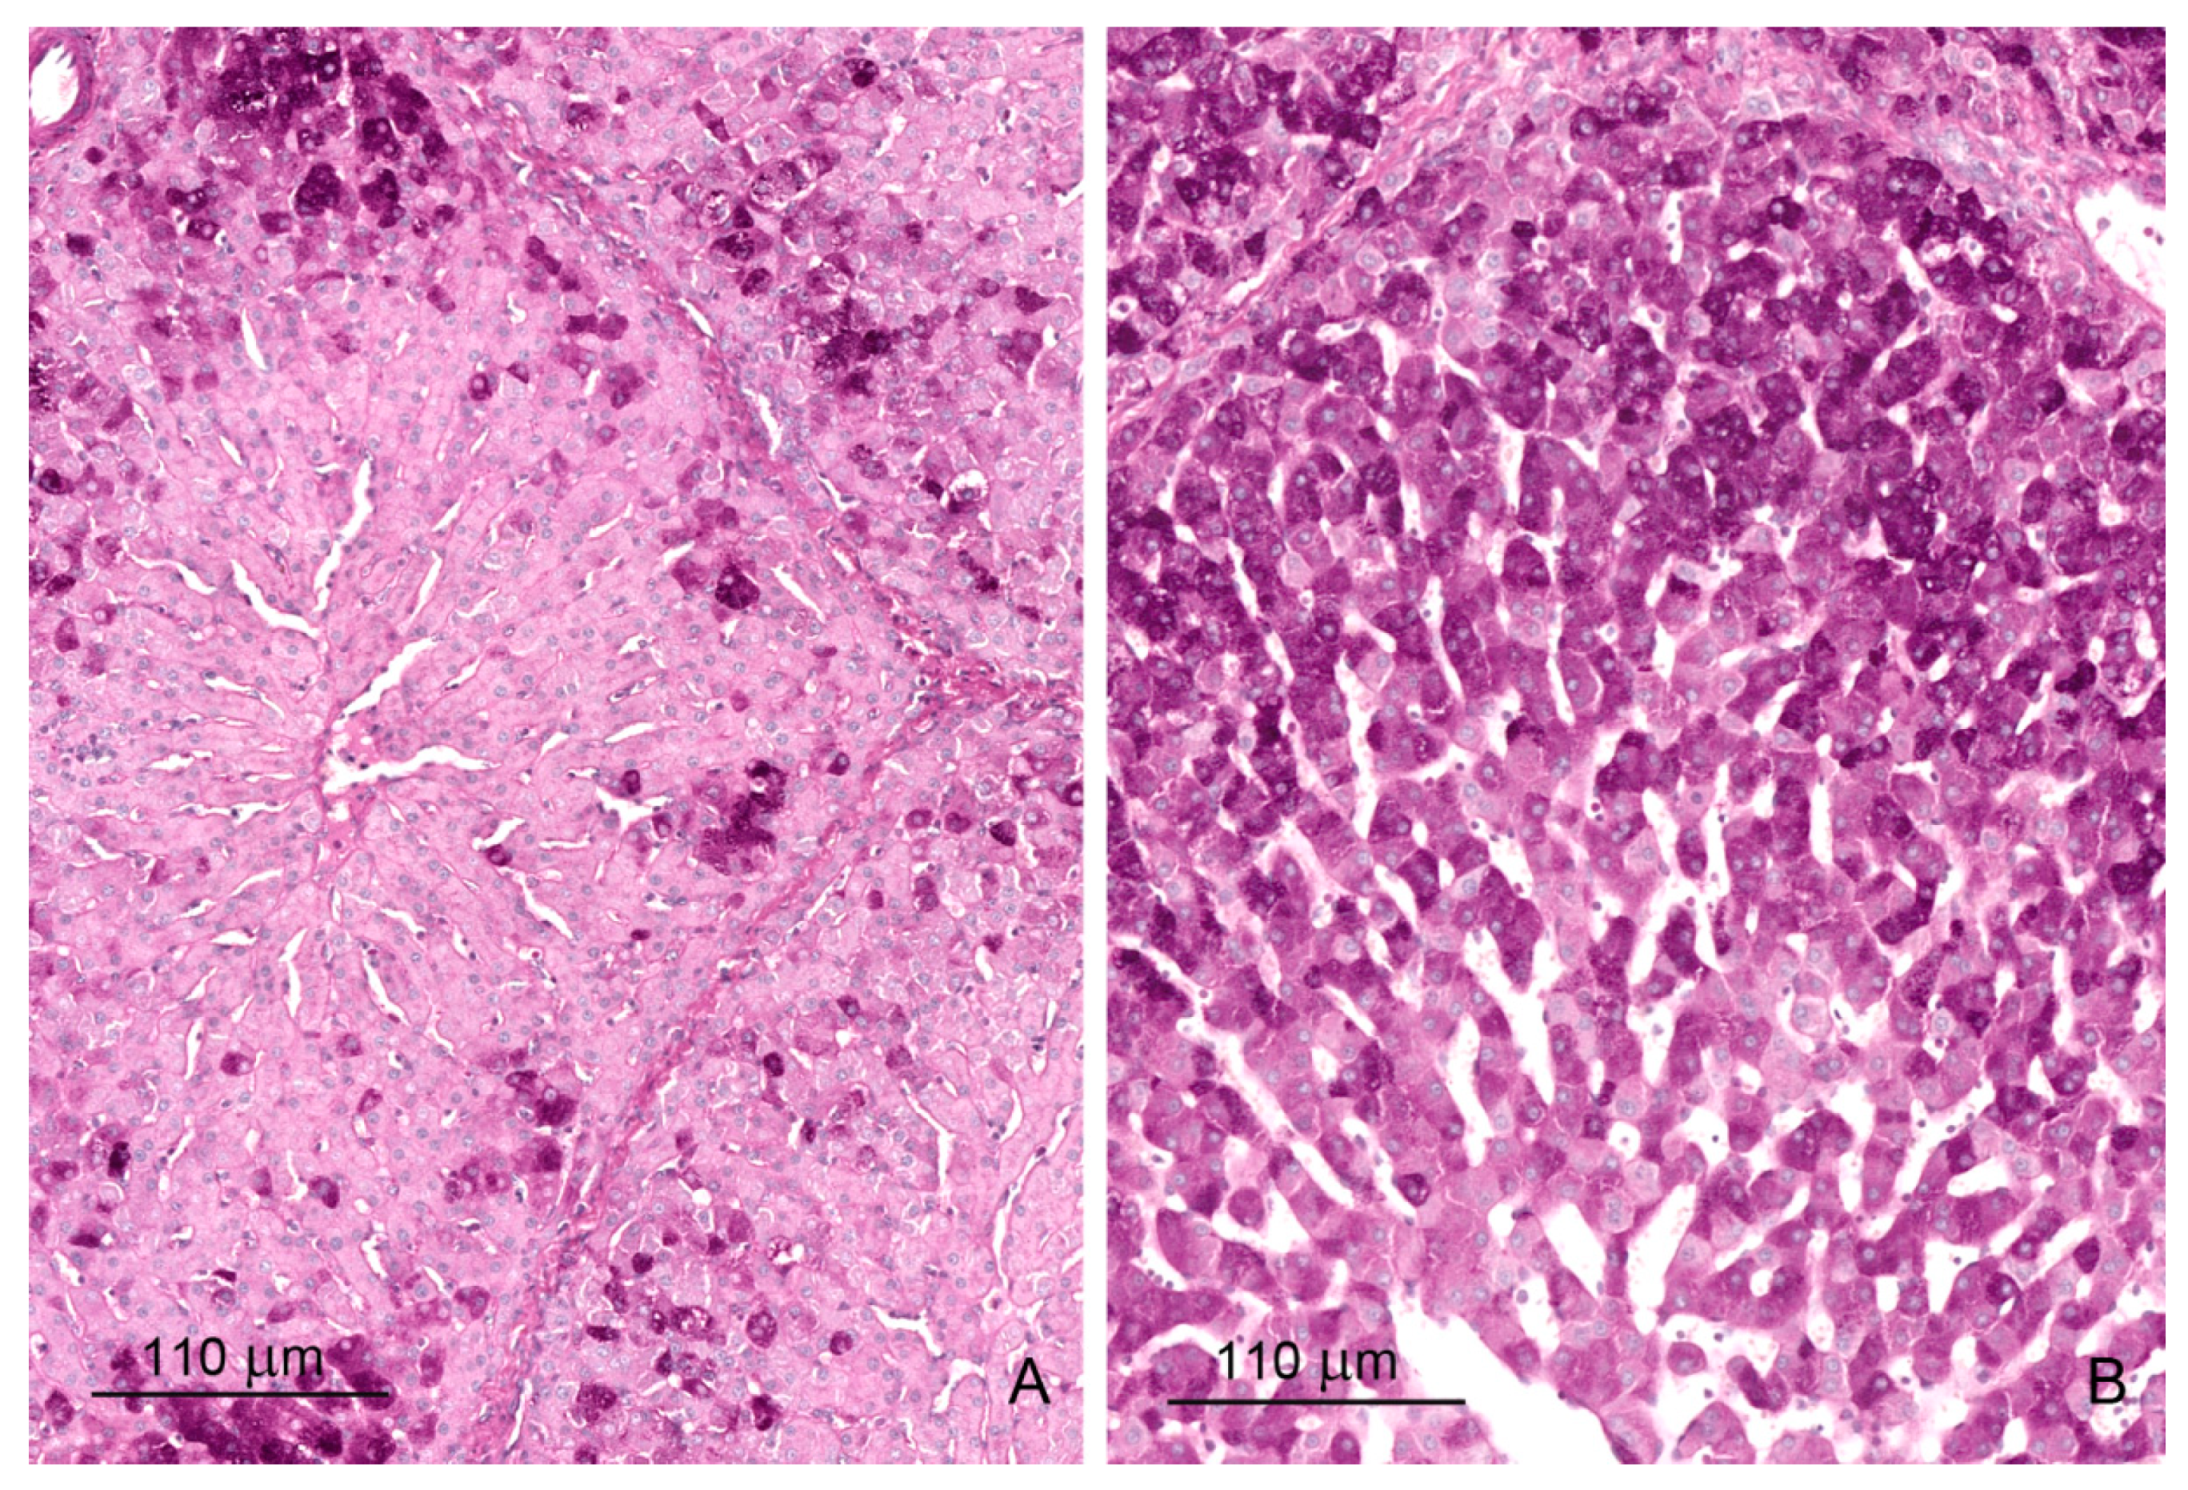

2.1. Light Microscopy Study

2.1.1. Architecture of the Liver

2.1.2. Microscopic Liver Scoring

2.1.3. Hepatic Sinusoids

2.1.4. Glycogen Storage

2.1.5. Iron Deposits